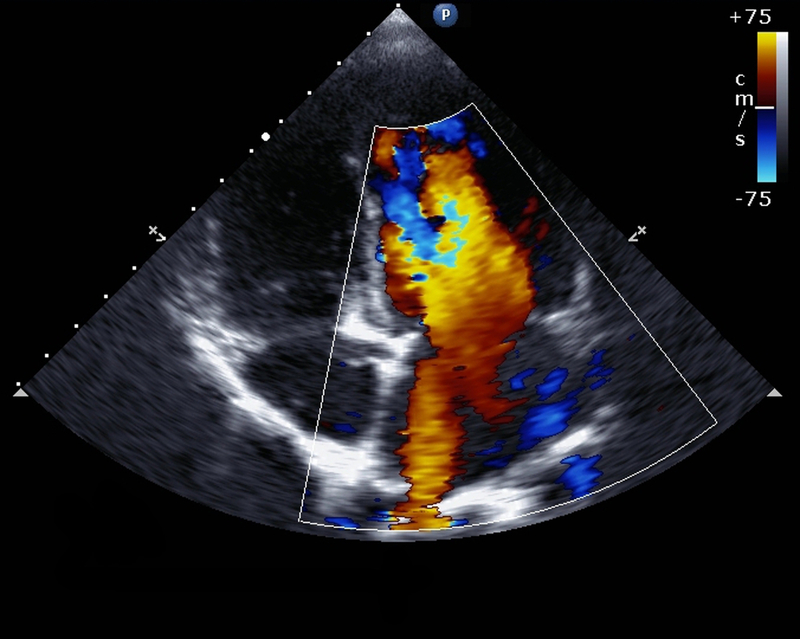

India Business Wire India Kiran Medical Systems, the radiology division of Trivitron Healthcare, has ventured into Color Doppler Ultrasound with the launch of Kiran SonoRad V9 Color Doppler in India.

SonoRad V9 is a Superior Color Doppler Ultrasound which can be used for wide range of clinical applications. The unique feature of the SonoRad V9 will further provide maximum value at an affordable cost and is ideal for Nursing Homes, Diagnostic Centres and Large & Mid-Size Hospitals.

SonoRad V9 comes with strong technical features like 38 cm depth penetration, 4D, Real Skin Imaging Tomographic Ultrasound Imaging, Panoramic Imaging, Real time Doppler auto-trace, Anatomical M-mode with special 3 cursors, advanced ergonomics with omni-directional mechanic arm and 19 LED Monitor with 170-degree wide view. It supports wide variety of probes to suit major applications like Obstetrics/Gynaecology, Radiology with high performance. SonoRad V9 supports cardiology features like TDI as well and CW/PW/HPRF is available with supporting probe. SonoRad V9 will be a right choice for multi-dimensional and whole body Color Doppler with a very high performance to cost ratio.